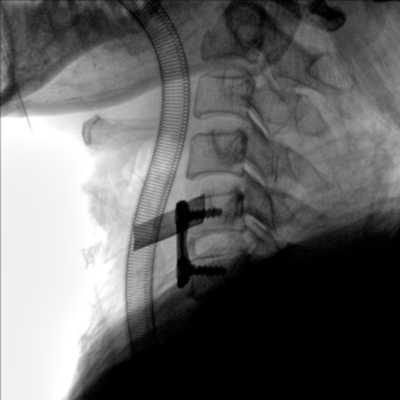

大尺寸動態(tài)平板探測器,高DQE、低噪聲、圖像清晰。采用多分辨率圖像增強處理技術(shù),不同部位不同圖像處理算法,滿足客戶多樣化的需求。

采用智能變頻脈沖透視技術(shù),優(yōu)化圖像質(zhì)量的同時降低輻射劑量,呵護醫(yī)患健康

圖形化操控界面設(shè)計:設(shè)有多種人體特征攝影參數(shù),操作簡便。雙向紅光十字定位系統(tǒng):實現(xiàn)無射線下的高效定位。信息共享:遵循DICOM3.0格式接口,可無縫對接云PACS系統(tǒng)。

多角度自由旋轉(zhuǎn),滿足患者復(fù)雜擺位需求。